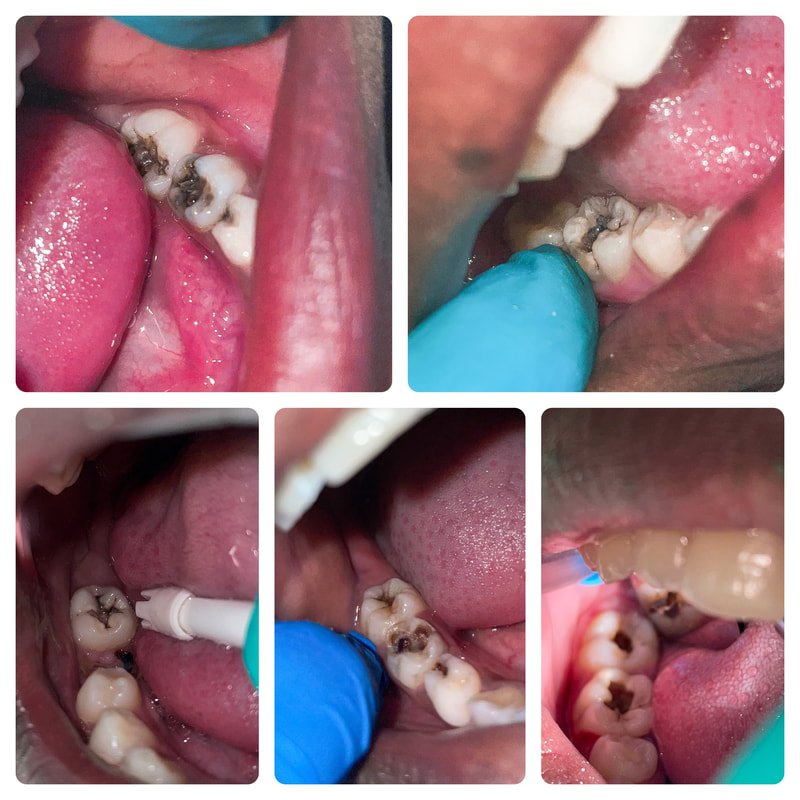

After a year of anticipation and several attempts that didn’t work out, God finally opened the door for Lisa to return solo for a much-awaited trip to see the kids. She had her hands full, as it had been a year since the children had received a proper cleaning. Many of the children also had urgent dental needs. Thanks to the generous donations of supporters, Lisa was able to partner with a local dentist, who generously offered his help over the course of two days. During this time, Lisa was able to provide each child with a thorough prophylaxis (cleaning), apply Silver Diamine Fluoride (SDF), and refresh sealants and fluoride varnish to safeguard their teeth.

As she worked through the list of patients, Lisa identified three boys who needed urgent dental care beyond her scope of practice. While there is no dentist in Bombardopolis, she had heard of one in a nearby town. Lisa and Frankie took the boys to see him for extractions, and the kids were so brave!